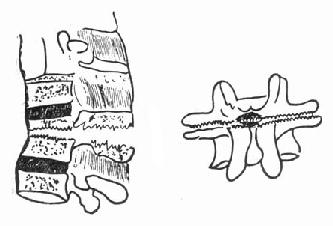

(一)单纯楔状压缩骨折的治疗 轻型的压缩骨折,可以采用保守治疗方法。天津医院骨科发掘我国古代医学遗产,创建了“垫枕背伸肌锻炼法”,是一种可行方法(图73-11)。具体做法为病人仰卧硬板床上,腰部用塔形枕垫起,垫枕正对骨折部位,保持脊柱过伸位。先静卧2~3天,待骨折处出血停止,疼痛减轻及腹气胀反应消退后即开始如图示方法,逐渐加强锻炼。病人卧床3个月,天天坚持锻炼,大部分病人可获得良好的结果(图73-12)。此法的缺点是需较长时间的卧床,且对一些比较严重的压缩骨折,有时复位不够满意。我们经验认为,对于椎体前方压缩50%以上者,特别是青年患者,最好用两根Harrington棍进行手术或Dick法复位固定。可以使骨折解剖复位,而且术后两周即可带石膏围腰或支具下地活动。

图73-11 垫枕背伸肌锻炼法

图73-12 垫枕背伸锻炼获良好结果

①骨折初时;②背伸锻炼3个月后

(二)旋转型脊柱骨折的治疗 用Harrington棍法,不能矫正旋转,最好用Luque棍或Dick法进行矫正与固定。两根“L”型金属棍,放在棘突基底两侧,用每一个椎板下穿过的Luque钢丝固定到骨折部位上、下方各三个椎体椎板上,通过弯好弧度的Luque棍的杠杆作用和拧紧Luque钢丝所产生的矫正力,可以矫正旋畸形,并牢固固定骨折。如不合并神经系统症状,1周后即可下地活动。

(三)爆裂型骨折的治疗 如不合并严重的神经系统症状,损伤又在两周以内者,可以用双Harrington法,撑开矫正,或用Dick手术;可以获得满意的结果(图73-13)。复位后需融合相邻两个椎间隙,因为CT常显示在爆裂型骨折中,相邻的上、下两个椎间盘均有损伤,如不融合,日后取棍后会出现腰痛。使用本法时,如前纵韧带完整,则很容易恢复椎体前方的高度。但爆裂型骨折存在下述三种情况时,需行前路减压术:①合并神经系统症状较重者;②就诊较晚,已两周以上者(常常10天以上就复位比较困难);③脊柱CT扫描显示已有较大的骨折片突出椎管内,使髓腔管变窄超过30%以上者,预示后纵韧带已有明显损伤,使用后路手术方法已无法使骨折片复位。Kostuik复习了日本和多伦多治疗脊柱骨折的结果后证实,前路减压术能使膀胱、肛门及肢体功能得到更好的恢复。

图73-13 爆裂型骨折的治疗 ①术前,骨折脱位;②术后,侧位;③术后,正位